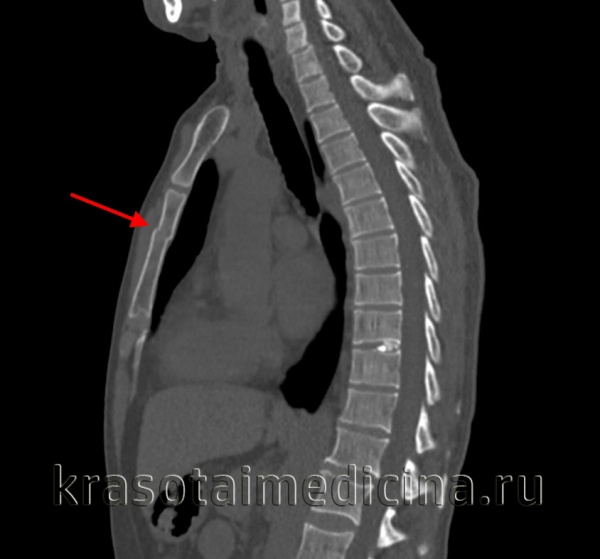

При судебно-медицинском исследовании трупа обнаружены не выявленные при жизни больного перелом тела девятого грудного позвонка с перерывом спинного мозга (!), значительное количество переломов ребер, повреждения печени.

Для подтверждения диагноза выполняют рентгенографию позвоночника в двух проекциях. При компрессионных переломах более информативен боковой снимок, на котором обычно четко определяется уменьшение высоты передних отделов тел позвонков (передние отделы как будто «сплющены»). В сомнительных случаях пациентов направляют на КТ позвоночника. При наличии неврологических нарушений назначают консультацию невролога или нейрохирурга.

При оскольчатых переломах на снимках выявляется расширение тела позвонка и уменьшение близлежащих межпозвонковых пространств. Снижения высоты позвонка, как правило, не наблюдается. В сомнительных случаях для более подробного изучения состояния костных структур и мягких тканей больных направляют на КТ и МРТ позвоночника. Пациентам с оскольчатыми переломами назначают консультацию нейрохирурга, миелографию и электрофизиологические исследования (ЭМГ, ЭНГ), а также выполняют ликвородинамические пробы.